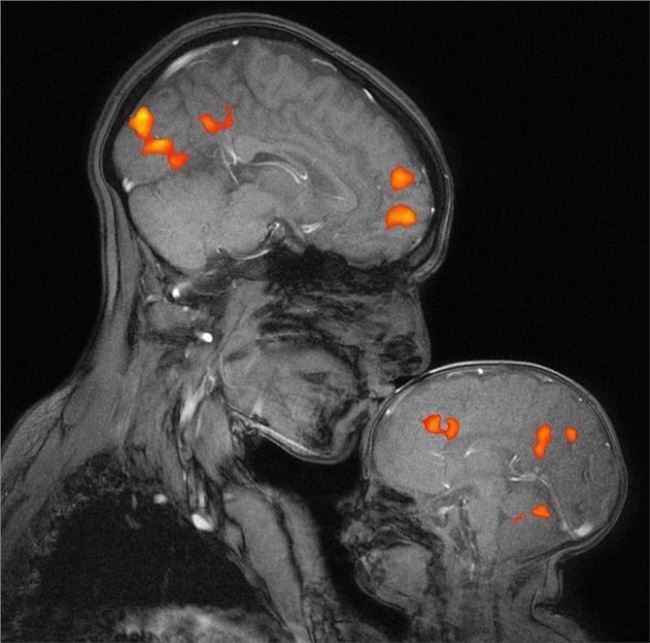

This is the first MRI capturing the brain activity of a mother kissing her child...

Her kiss has caused a chemical reaction in her baby’s brain. Source Credit : @rebecca_saxe , @MIT